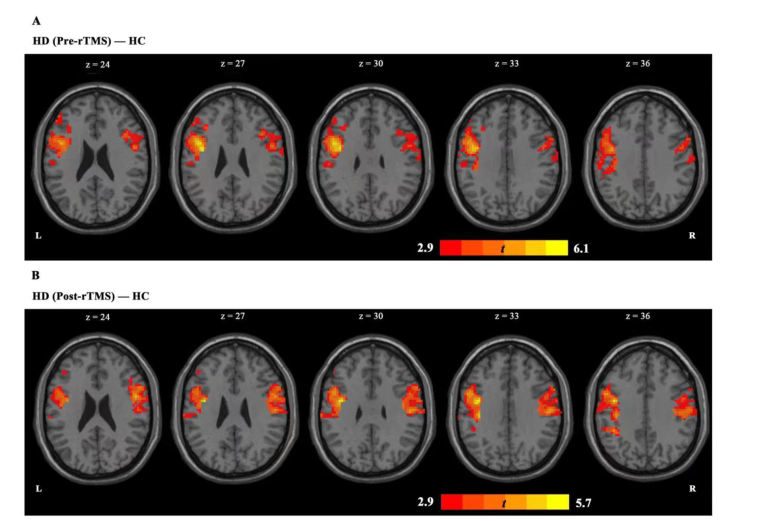

上图显示,在基于 PCC 的分析中,我们发现 HD 组与 HC 组相比表现出 PCC-左额下回,PCC-右侧中央前回耦联增加。

在完成 7 个疗程的 rTMS 疗程后,HD 组的 PCC-左额下回耦合异常增加后出现了减少,并在HC组表现出类似的趋势。但在治疗后,(HDvsHC)pcc-右中央前回耦联持续存在。